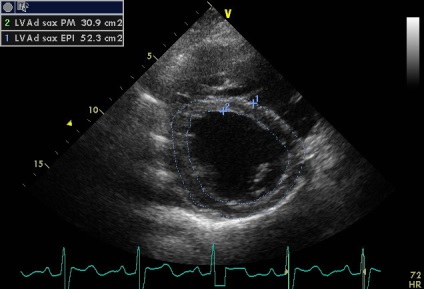

Bizonyíték van arra, echokardiográfia évvel ezelőtt, amely leírja egy kis kiterjesztése aortagyökben, aszimmetrikus aortabillentyű ( „funkcionális bikuspidiya”), egy kisebb aorta regurgitatio.

Sinus Valsalva - egy zseb-szerű szerkezet határolt szálas gyűrűt szelepcsappantyú, és az illető semiiunaris aorta fal, annak felső határa - sino-csöves csatlakozás. A falakat a két szinusz van a szája, a jobb és a bal koroanrnyh artériák, és hívják a jobb és a bal koszorúér sinus, és a maradék egyharmad - a nem koszorúér. A beteg egy diszkontinuitás az aneurizma a jobb coronaria sinus Valsalva (ünnepelte gyakrabban), mint látható parastrenalnyh szakaszok rövid és hosszú távú (egy lejtőn) tengelyeken. Számos egyéb, kevésbé gyakori aneurizma orrmelléküregek, még kevésbé egyidejűleg 2 vagy 3 (nem tévesztendő össze egy egyszerű kiterjesztése aortagyök szintjén az orrmelléküregek, ellentétben, amelyek továbbra is legyen tarsoly alakú kiemelkedés a fal, mint a mi beteg). A formáció egy ilyen aneurizma egy patológiás állapottal vegyületet struktúrák bázis szelep szórólapok és aorta fal. Fistulák (kóros anasztomózis) a szinuszok szintet, és anélkül, aneurizma (pl, amely különféle fertőző endocarditis). Csakúgy, mint az aneurizma nem bonyolítja egy hosszú szünet (és általában nem, hogy klinikailag). A rés a kialakulását a sipoly kiváltható trauma, szívbelhártya-gyulladás, magas vérnyomás, stb de néha spontán. A szünet alakul súlyos volumen túlterhelés, olyan funkciókkal, hemodinamikus megnyilvánulások, attól függően, hogy melyik kamrában visszaáll az aortából. Ebben az esetben, a reset határozzuk meg a jobb kamrai kiáramlási traktus (2. típusú), egy jelentős növekedést véráramlást a bal kamrai kiáramlási traktus (disztálisan a sipoly, miközben a szisztémás keringésbe csökken). Drámaian megnövekedett a nyomás a jobb kamra (amint azt a gradiens tricuspidalis regurgitáció + jelei megnövekedett nyomás a jobb pitvarban). De pulmonális sávval egy reflexszerűen hipovolémia, amíg részlegesen „védett” (görcs) az ilyen akut volumen túlterhelés (fokozott jelei rezisztencia lehet számítani). A helyzet sürgető, és előírja szívsebészet.